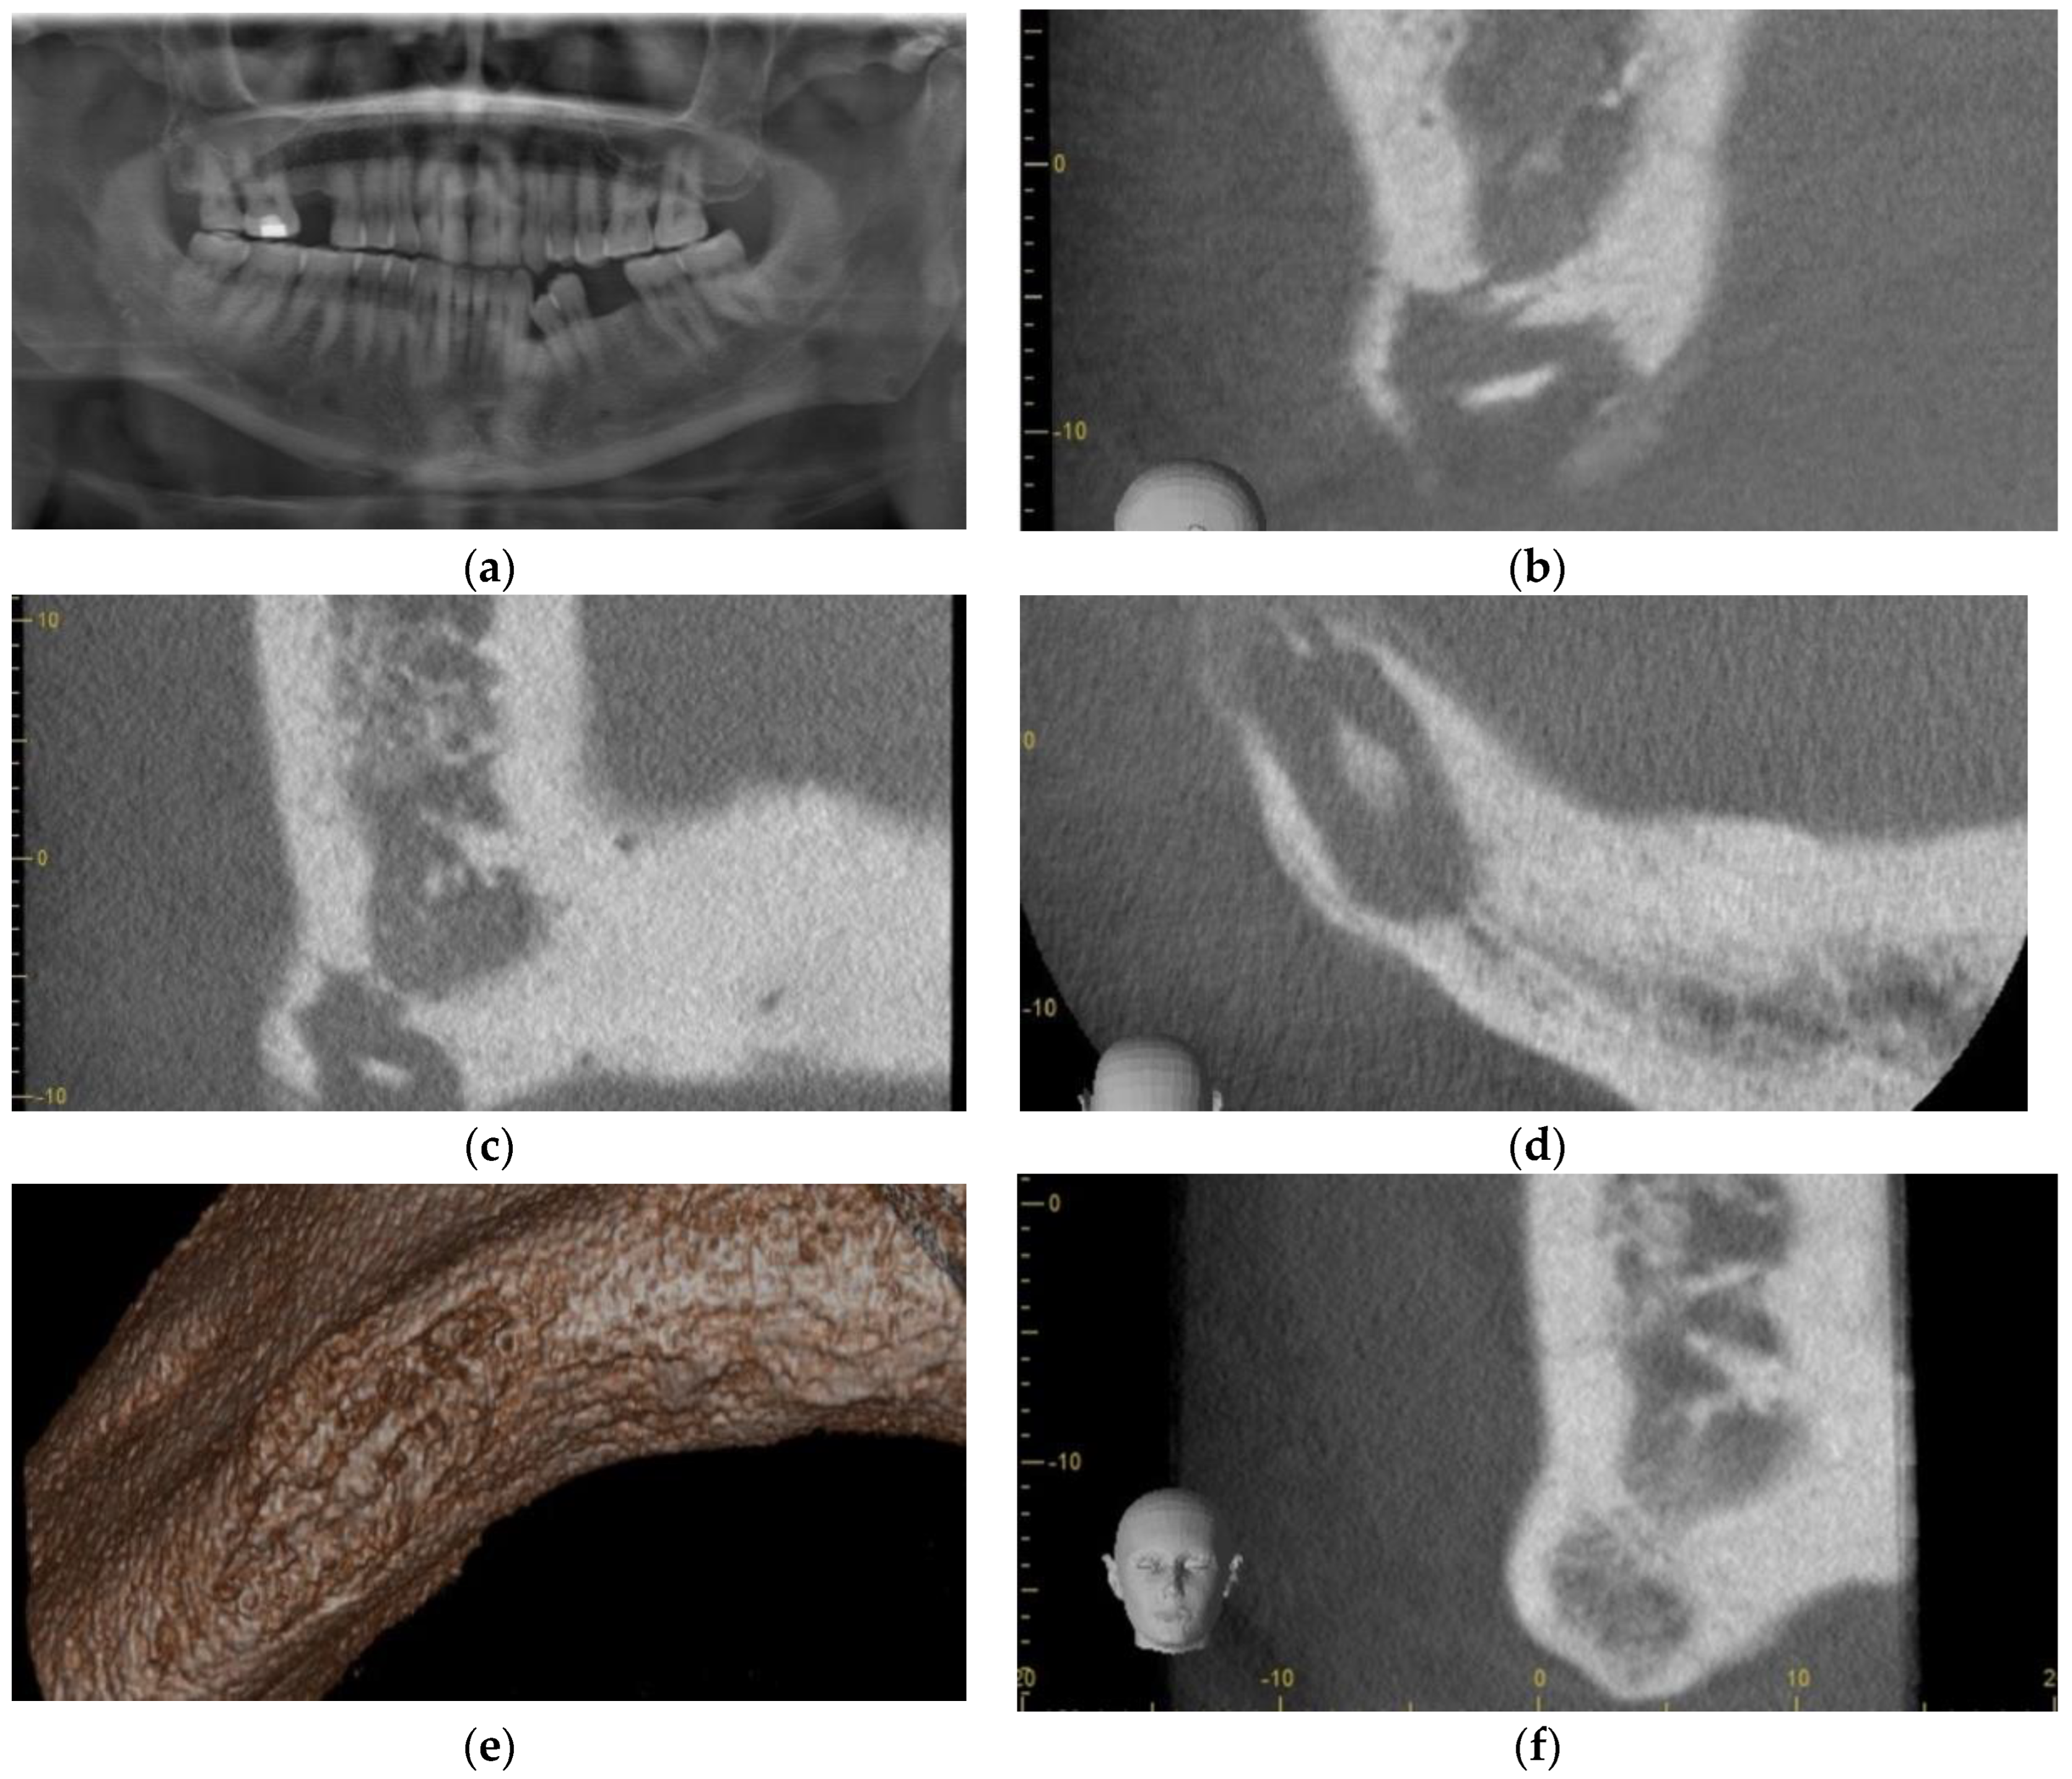

3.3. Case 3

3.4. Case 4